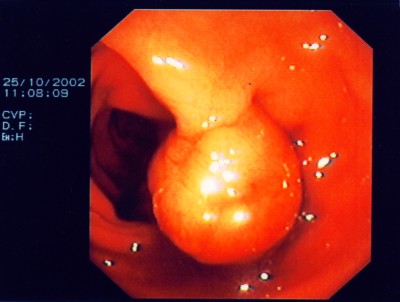

Großer Polyp des Dickdarmes